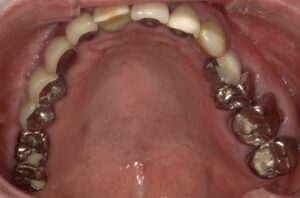

このように奥歯にしっかりとインプラントが

入りました。

歯が増えています。